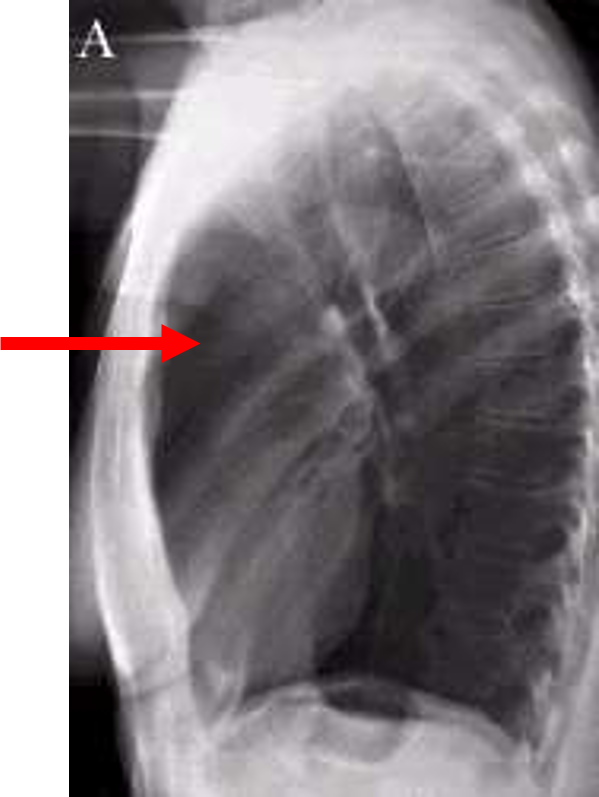

lateral chest

three rules of a lateral chest x ray

diaphragm shadow

retrosternal space

retrocardiac space